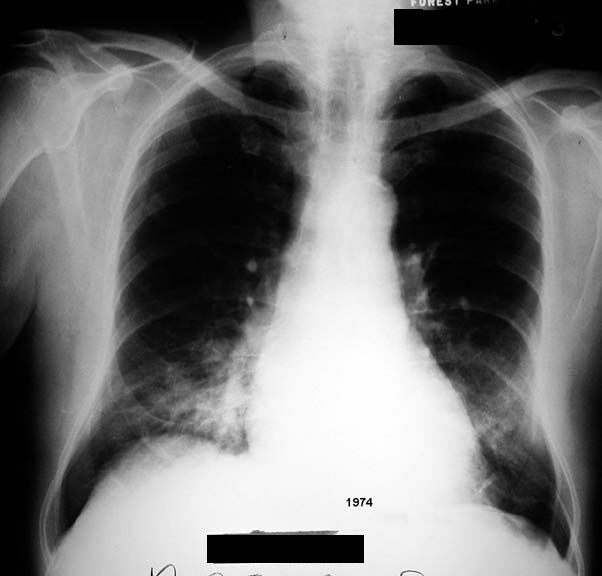

Lipoid Pneumonia

• Alveolar

• Mass like densities

• Chronic

• Lower lung fields

• Bilateral in this case

See lateral and sequential films below.

Air space density projecting over RML and lingula